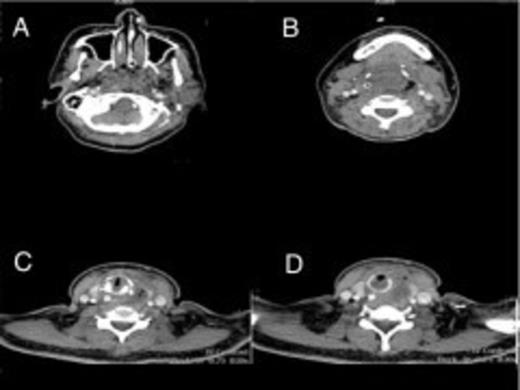

Upon arrival at Accident and Emergency Unit in our hospital, she developed acute respiratory distress with stridor. Fiberoptic Nasopharyngolaryngeal intubation was attempted but due to the severe edematous larynx, the procedure was abandoned. An emergency tracheostomy was then performed. CT scan showed pus collection in two areas:

Retropharyngeal region extending to the left parapharyngeal space measuring 6.9cm x 3.5cm x 2.9cm from level of C2-C7 extending into left side of neck just medial and anterior to the left carotid sheath

Lateral to the left thyroid cartilage measuring 3.0cm x 2.0cm x 2.9cm (Fig. 1&2)

Serial contrast enhanced axial CT images at (A) the level of the nasopharynx show complete occlusion of the air passage, (B, C, D-blue arrows) the level of the oropharynx and hypopharynx with ill defined rim enhancing cavities and air pockets on the left and around the right carotid sheath